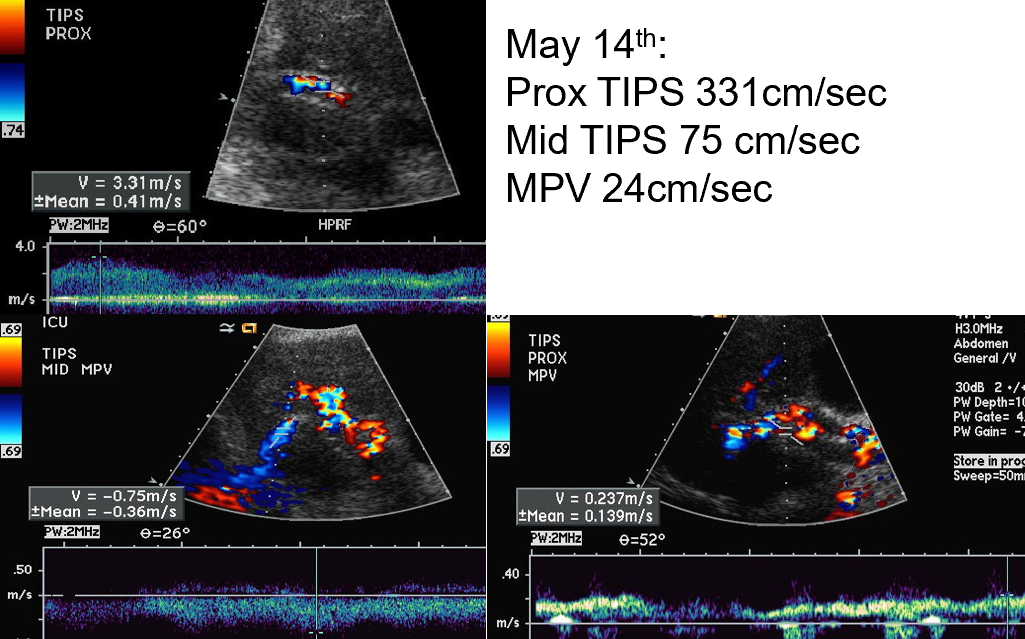

case example

mid TIPS velocities are 50cm/s → below normal

distal TIPS velocities are 251 cm/s → above normal

LPV is flowing in ‘normal direction’

should be hepatofugal flow with TIPS

Conclusion

stenosis of distal TIPS

what does this show?

prox TIPS velocity → HIGH

mid TIPS velocity → low

MPV velocity → low

Conclusion : PT required a TIPS revision

downstream stenosis reduces forward flow → velocity drops upstream